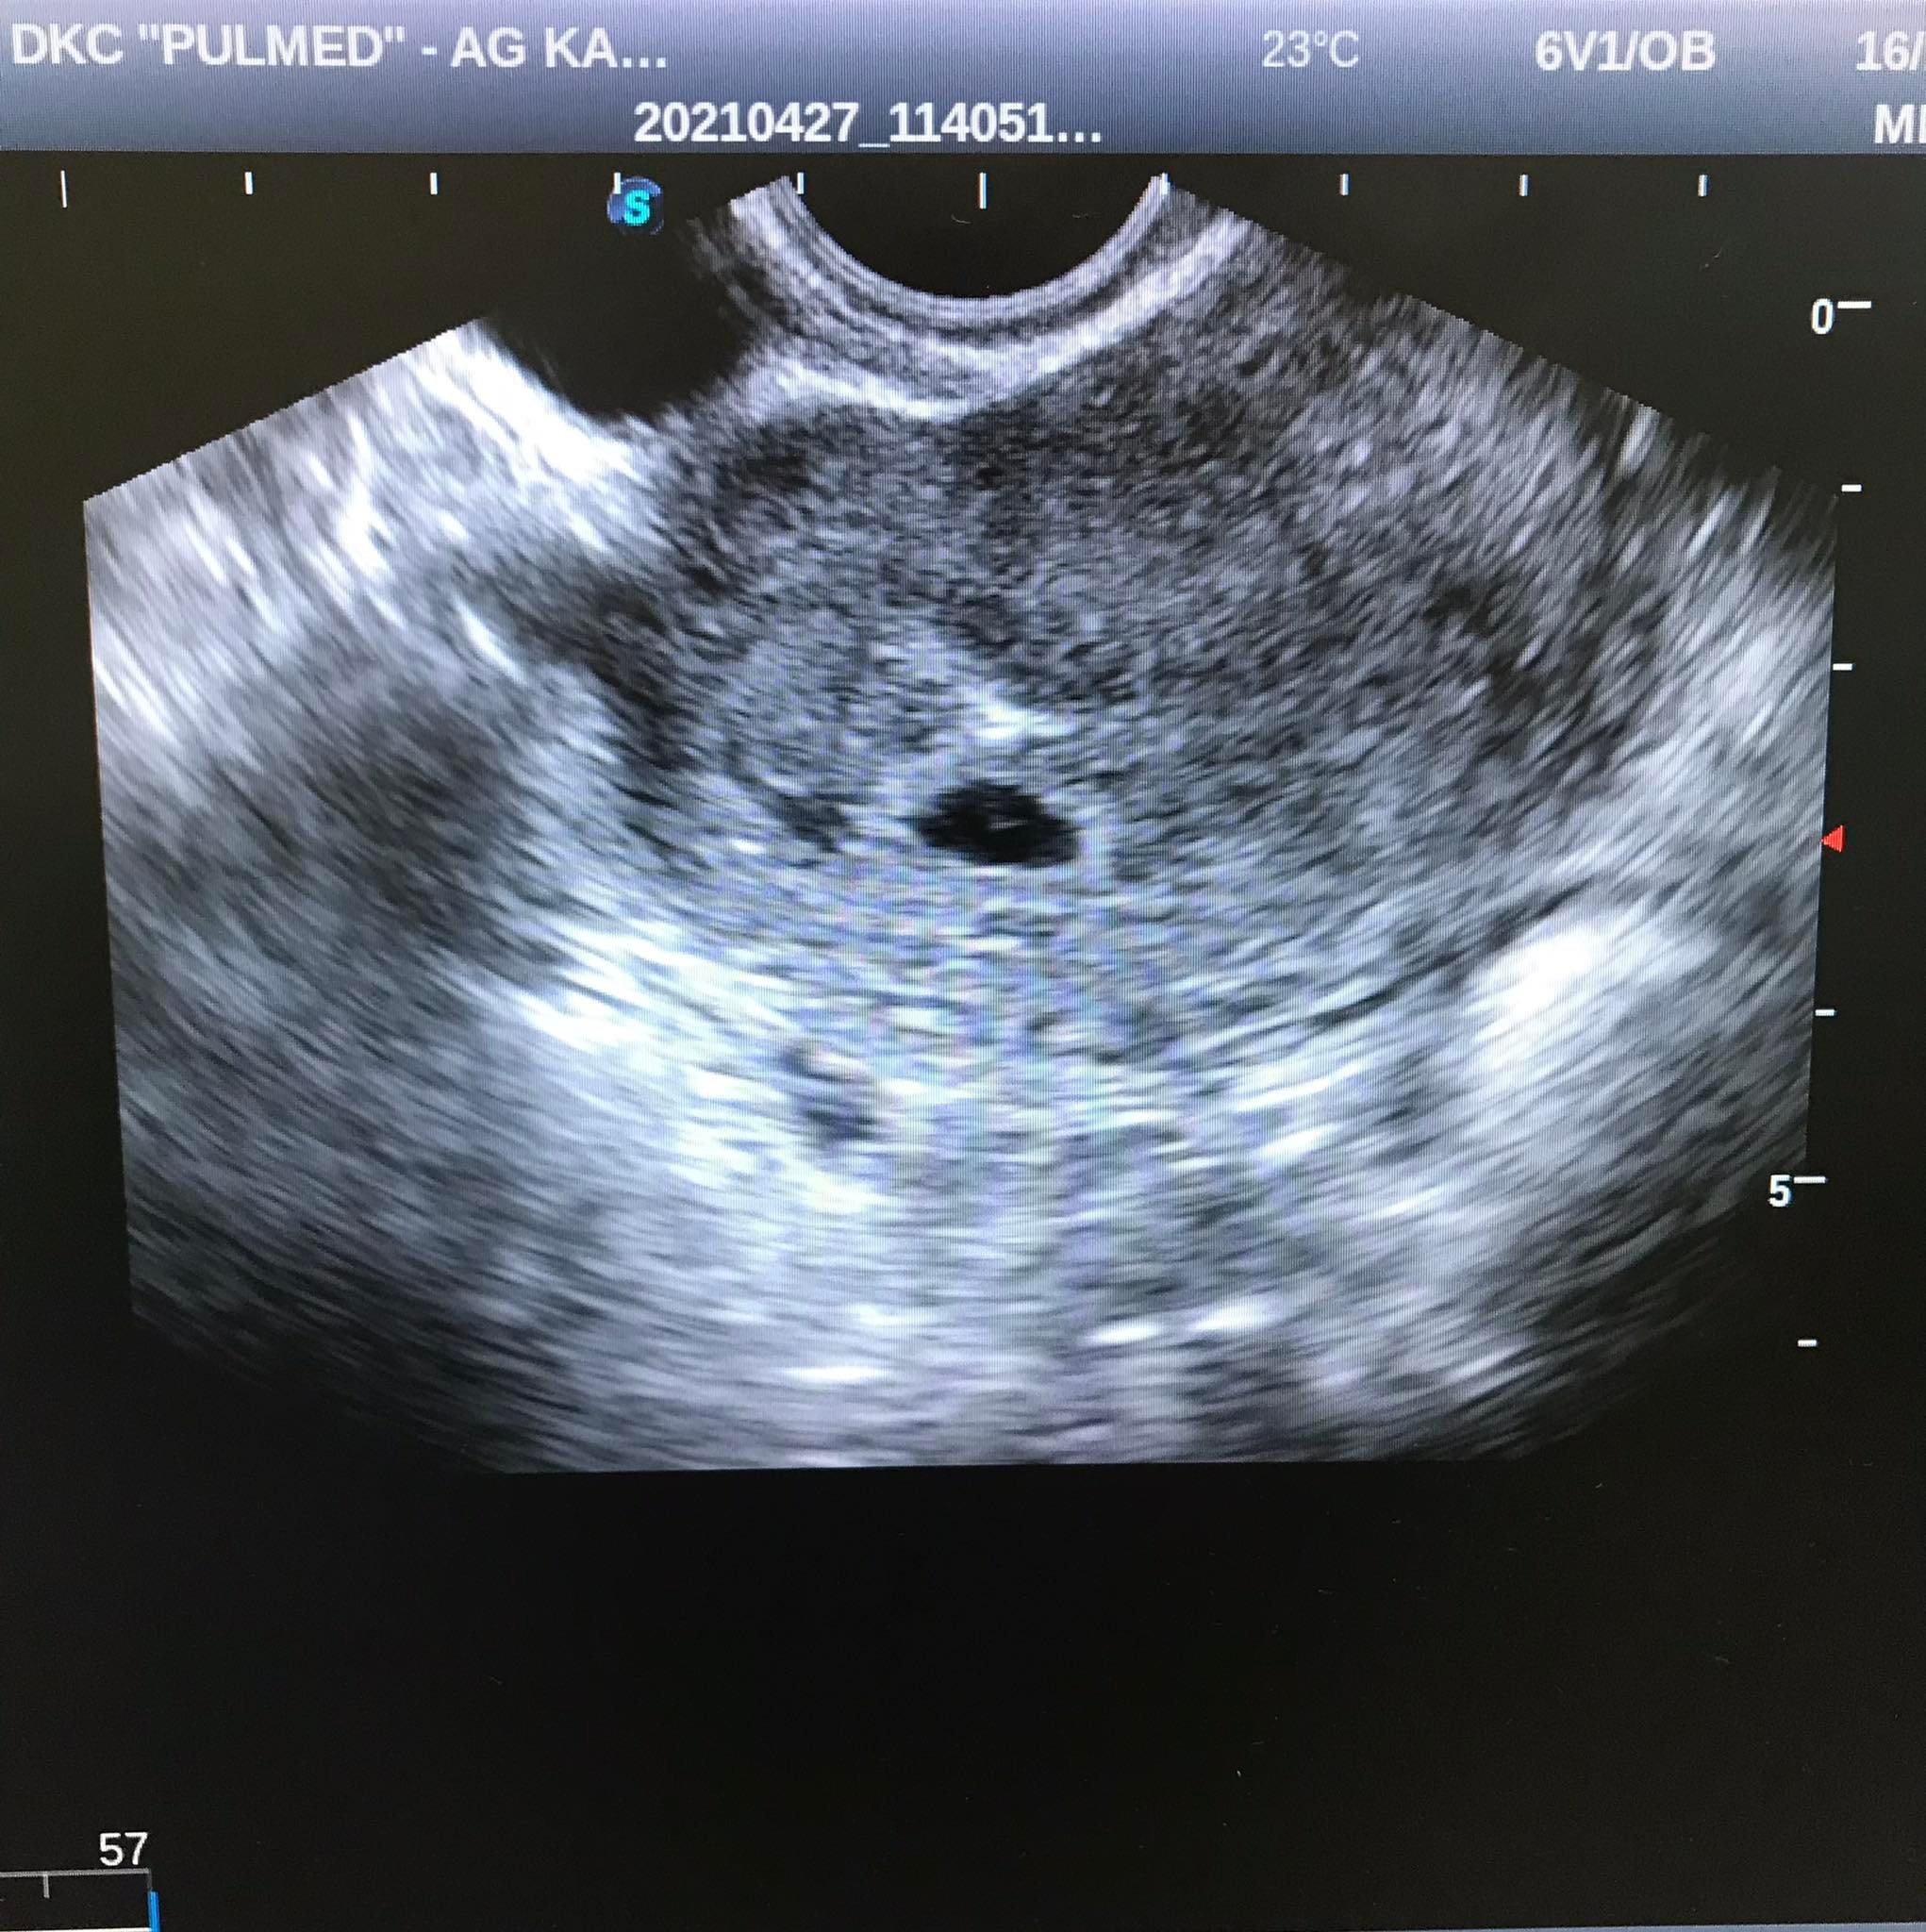

, тъй като съм 5+6 и според АГ термина ми е на 19.07.2022г.

но продължаваме напред и чакаме с нетърпение следващия преглед, когато ще чуем

и да се надяваме всичко да бъде наред. Успех на всички и леко бременеене